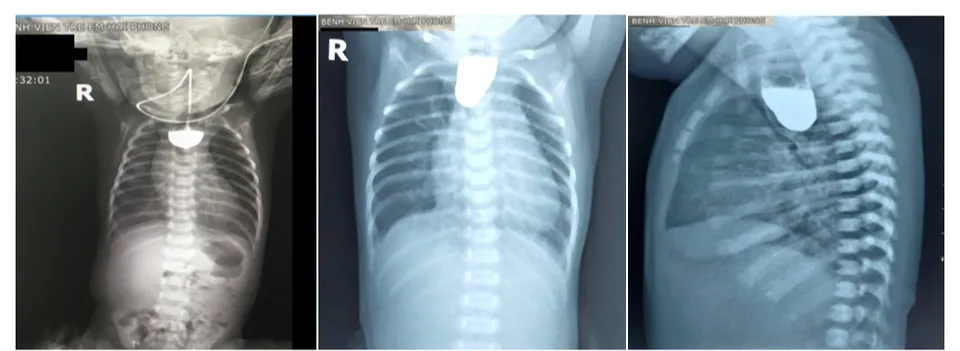

Teo thực quản được định nghĩa là sự gián đoạn lưu thông thực quản kèm theo có hoặc không có sự thông thương bất thường giữa thực quản với khí quản. Hiện nay, mặc dù có những tiến bộ về phẫu thuật nối thực quản và hồi sức nhưng teo thực quản vẫn còn là một bệnh có tỷ lệ tử vong cao do thường kèm dò khí quản - thực quản gây viêm phổi hít.

Teo thực quản có thể được chẩn đoán sớm ngay từ trước khi sinh bằng phương pháp siêu âm ở 24 tuần tuổi. Những trẻ bị mắc bệnh teo thực quản thường phải được phẫu thuật để giúp trẻ có cơ hội sống cao hơn, nếu để lâu dễ dẫn đến nguy cơ viêm phổi, tăng áp phổi làm bệnh thêm trầm trọng. Việc phát hiện bệnh sớm có vai trò vô cùng quan trọng trong điều trị, nếu phát hiện muộn, hoại tử ruột có thể gây ra nguy hiểm cho bệnh nhi.

Thường với những trẻ bị teo thực quản bẩm sinh, phương pháp điều trị phổ biến và hiệu quả nhất là phẫu thuật. Các bác sĩ sẽ thực hiện phẫu thuật khâu hai đầu thực quản lại với nhau nếu trẻ bị teo thực quản tạo khoảng cách nhẹ. Điều này giúp thông đường tiêu hóa từ miệng tới dạ dày.

Đối với những trường hợp teo thực quản khoảng cách quá lớn, bác sĩ sẽ thực hiện phẫu thuật lấy một đoạn ruột đưa lên để ghép nối với thực quản. Hoặc các bác sĩ có thể đưa đầu trên thực quản ra cổ, mở thông dạ dày để cho trẻ ăn. Trẻ sẽ được phẫu thuật tạo hình thực quản sau 6 tháng.